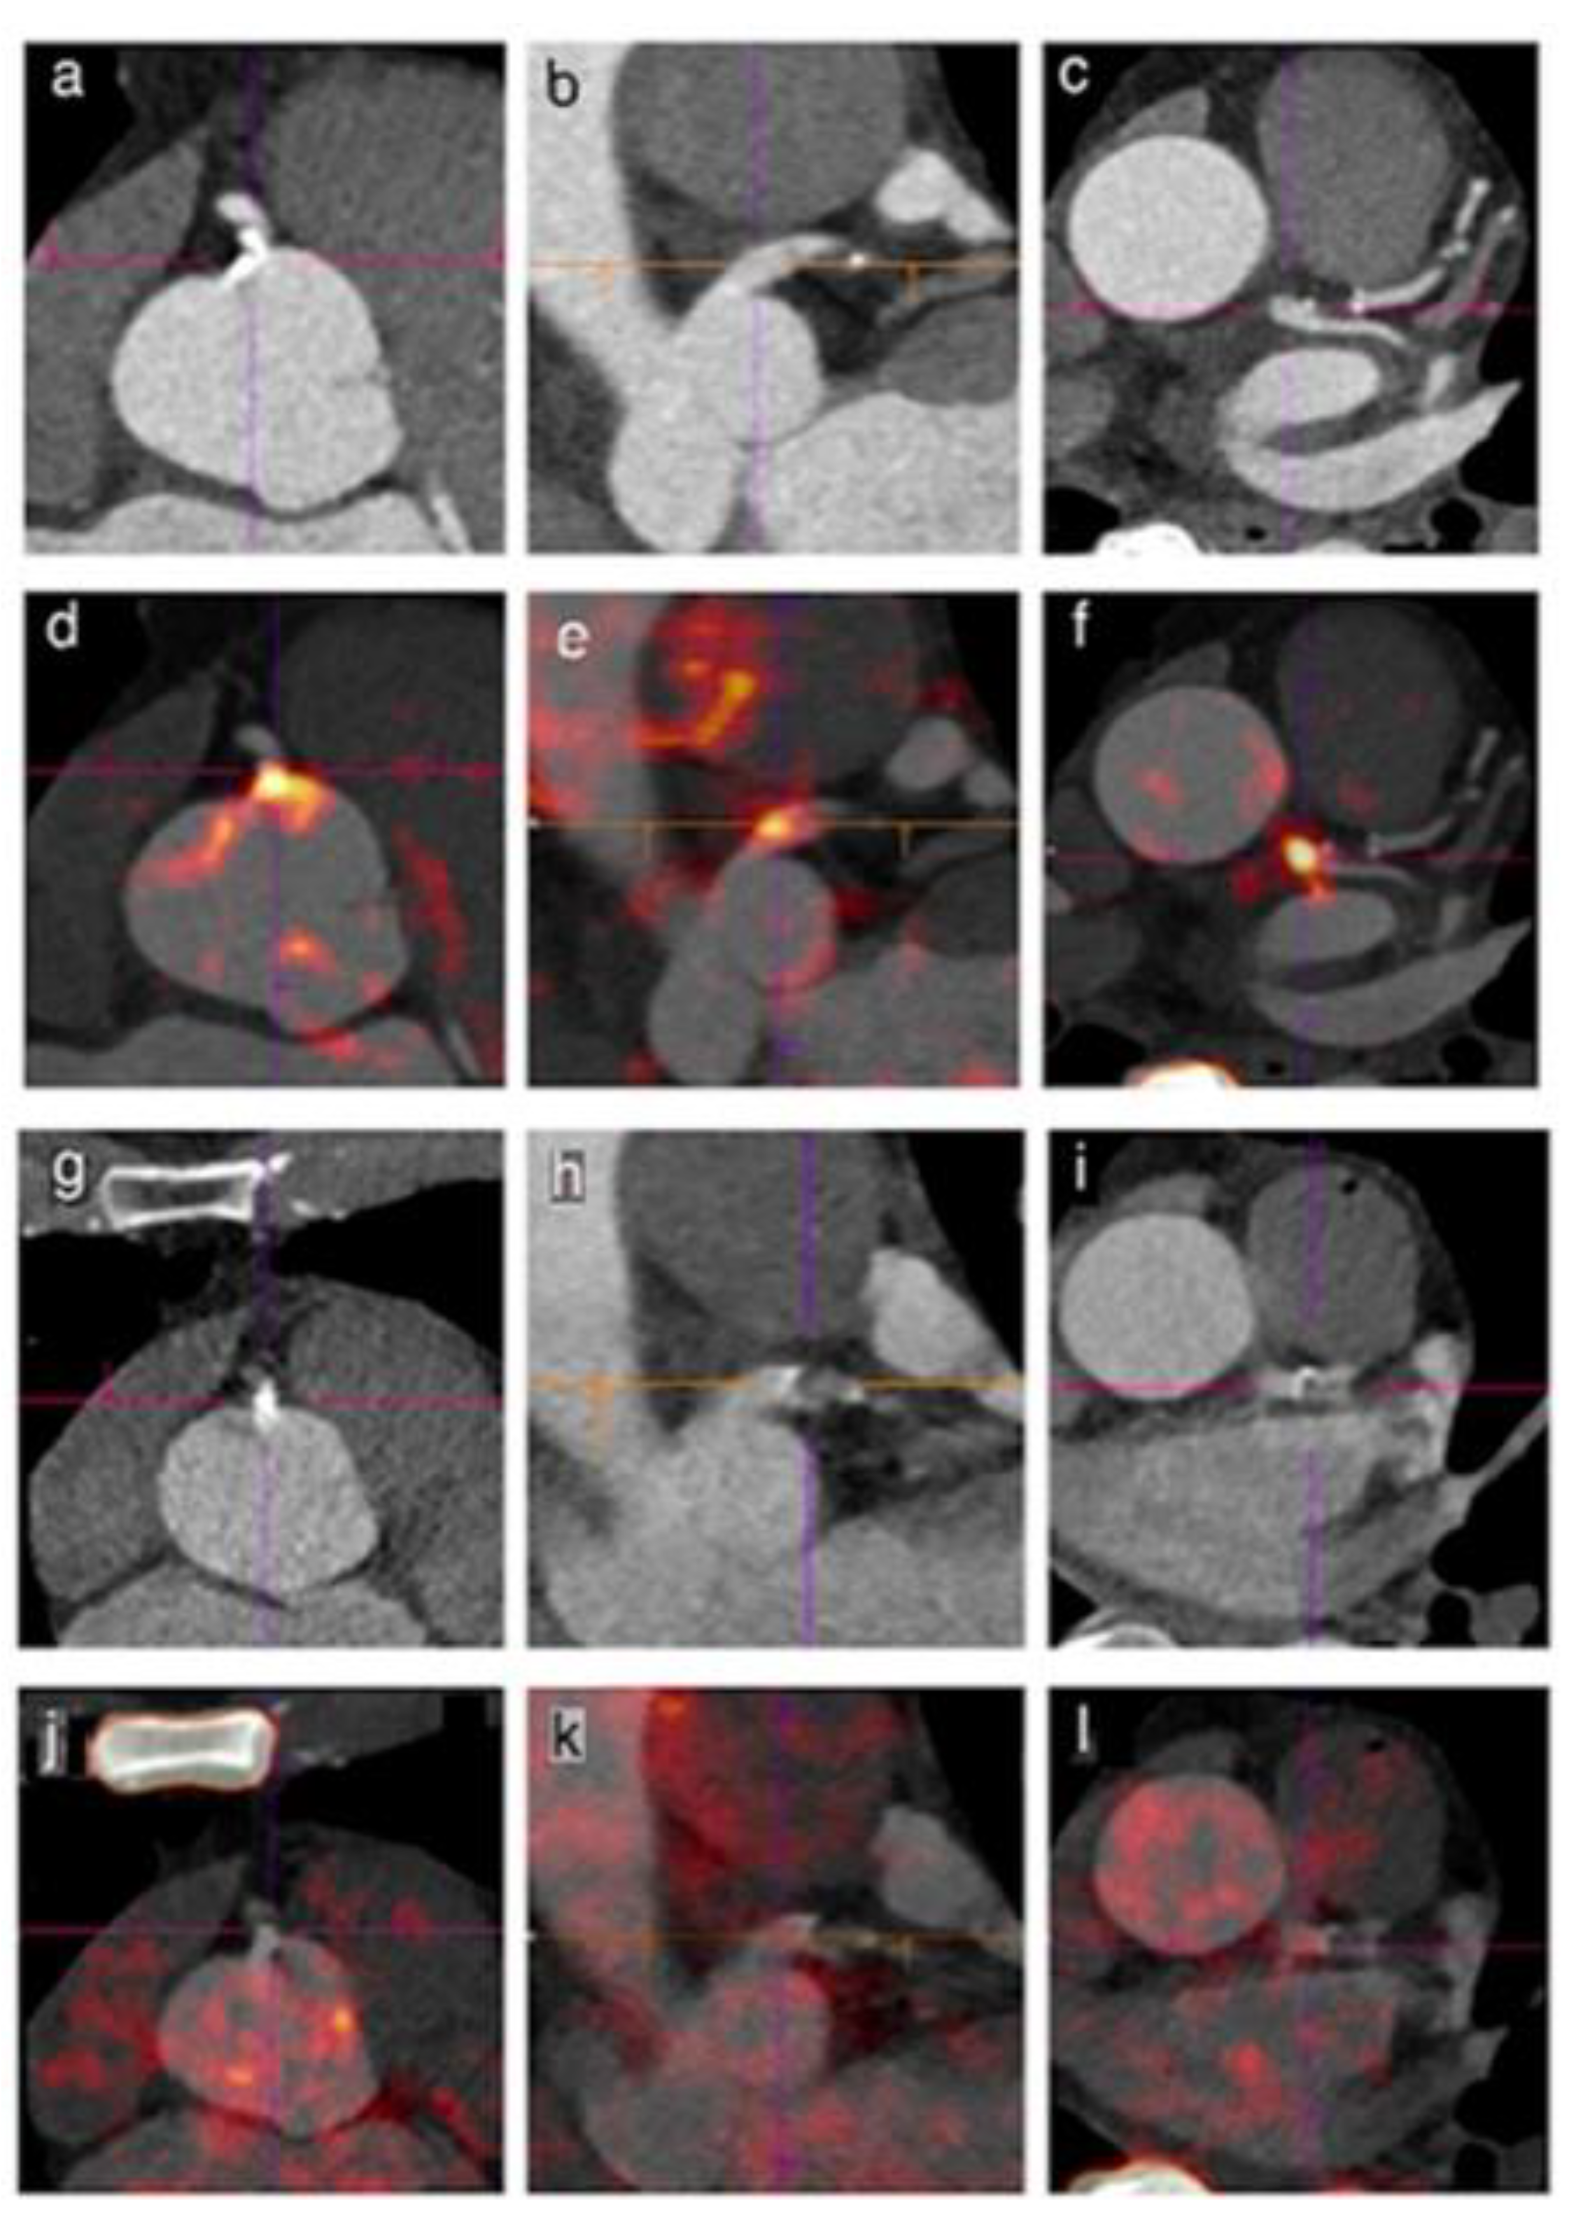

- McKenney-Drake, M.L.; Moghbel, M.C.; Paydary, K.; Alloosh, M.; Houshmand, S.; Moe, S.; Salavati, A.; Sturek, J.M.; Territo, P.R.; Weaver, C.; et al. 18F-NaF and 18F-FDG as molecular probes in the evaluation of atherosclerosis. Eur. J. Nucl. Med. Mol. Imaging 2018, 45, 2190–2200. [Google Scholar] [CrossRef]